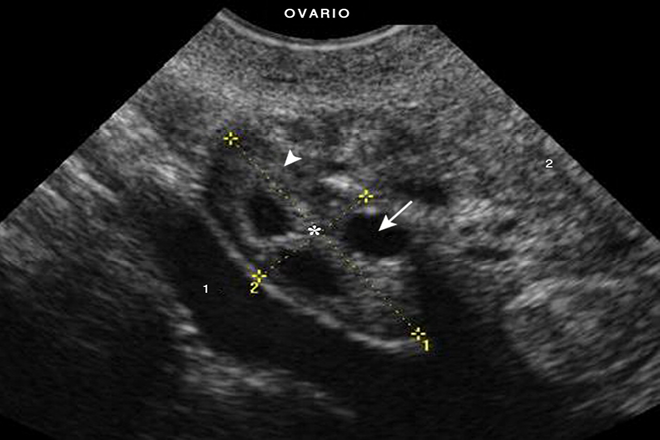

Una vez que el transductor está en su lugar, el médico o la técnico de ultrasonido buscará quistes en los ovarios. Los quistes aparecerán como sacos llenos de líquido en la imagen de ultrasonido. El médico o la técnico de ultrasonido medirá el tamaño de los quistes y evaluará su apariencia para determinar si son benignos (no cancerosos) o malignos (cancerosos).